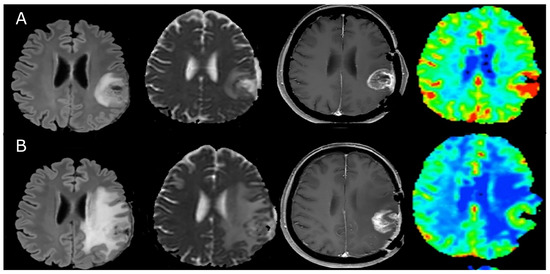

- Zhou, J.; Tryggestad, E.; Wen, Z.; Lal, B.; Zhou, T.; Grossman, R.; Wang, S.; Yan, K.; Fu, D.X.; Ford, E.; et al. Differentiation between glioma and radiation necrosis using molecular magnetic resonance imaging of endogenous proteins and peptides. Nat. Med. 2011, 17, 130–134. [Google Scholar] [CrossRef]

- Ma, B.; Blakeley, J.O.; Hong, X.; Zhang, H.; Jiang, S.; Blair, L.; Zhang, Y.; Heo, H.Y.; Zhang, M.; van Zijl, P.C.M.; et al. Applying amide proton transfer-weighted MRI to distinguish pseudoprogression from true progression in malignant gliomas. J. Magn. Reson. Imaging 2016, 44, 456–462. [Google Scholar] [CrossRef]